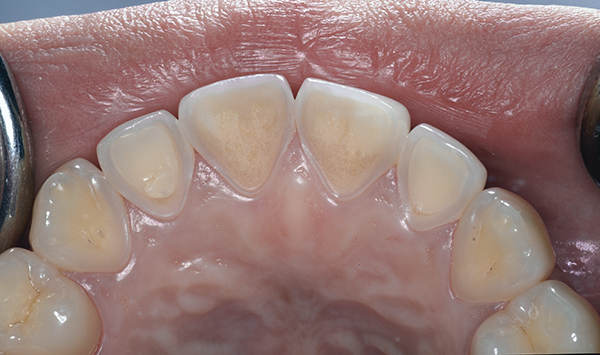

(Figure 4.) Gingival recession with exposed root surfaces are susceptible to dentinal hypersensitivity facial surfaces of maxillary teeth with recession with symptoms of dentin hypersensitivity.

A major predisposing factor to dentin hypersensitivity is exposed root surfaces (Figure 2 through Figure 4).33 Contributors to dentin hypersensitivity include enamel loss with exposed dentin due to attrition and tooth wear caused by bruxism, occlusal habits, and parafunctional activity (Figure 5).34